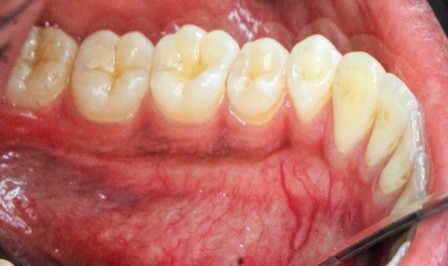

The MGJ was delineated by the visual method and the roll method following clinical examination in dental chairs appropriately equipped. Visual assessment relies on identifying the color difference between the gingiva and alveolar mucosa. The mucosa beyond the MGJ typically appears darker red compared to the AG, helping to demarcate the MGJ. The rolling probe method entails pushing the neighboring alveolar mucosa coronally with the blunt end of a probe. It is a functional assessment method that aids in determining the boundary between gingiva and movable mucosa.10 The probing sulcus depth was subtracted from the measured KG width at the mid-lingual aspect of each tooth to determine the width of AG, and all fractional measurements were rounded off to the nearest whole number of millimeters (Figure 1 through Figure 3).

Fig 2 = sulcus depth measurement.

Figure 2